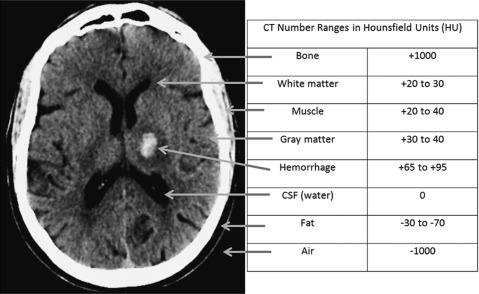

Hounsfield Units

Different Tissues, Different Intensities

measure of the reduction intensity of a ray of light by the tissue through it passes